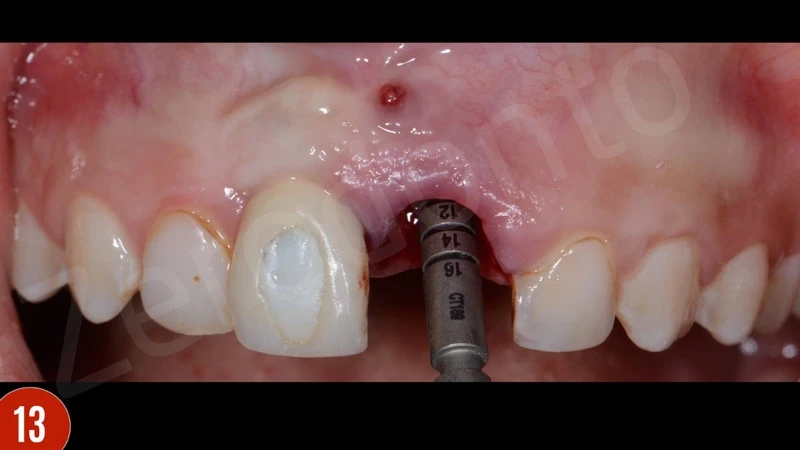

Sau khi nhổ răng, mô hạt đã được loại bỏ cẩn thận. Khoan xương phía khẩu cái cung cấp sự ổn định chính và đặt phục hình tạm thời. Để bảo vệ các đường cong phía môi, khoảng trống giữa bản xương phía môi và implant được ghép với xương bò khử khoáng. Phục hình tạm thời được gắn vào implant tại lực torque 15 Ncm.